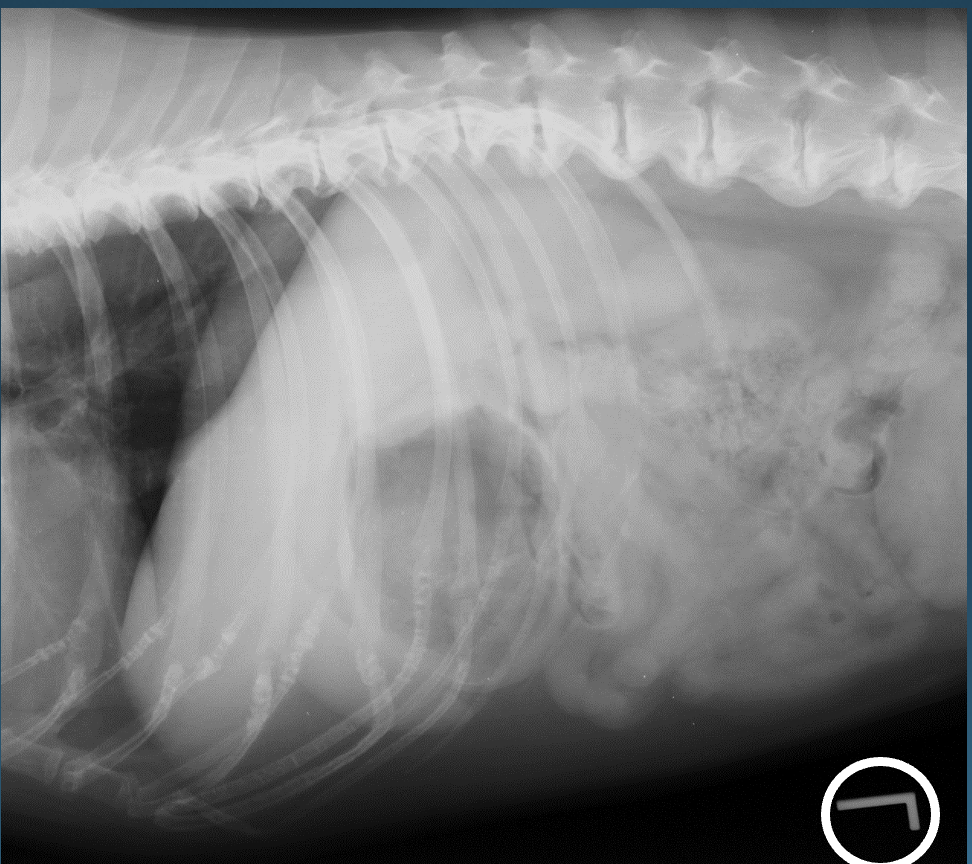

What is shown in these images?

normal large intestine in the dog

What is shown in this image?

normal colon